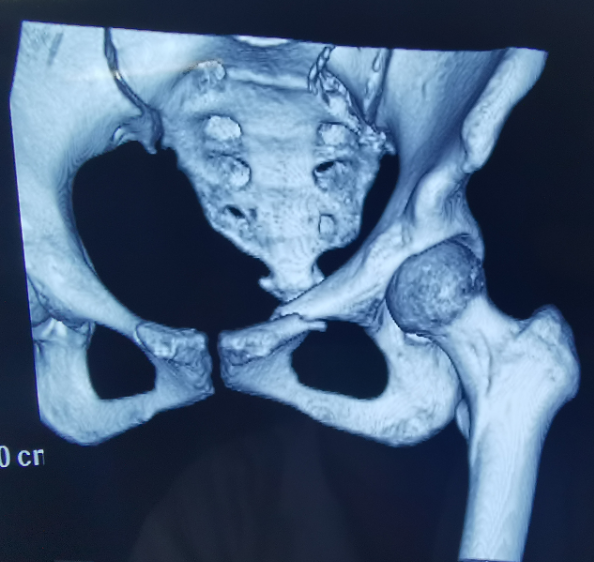

患者为22岁年轻女性,因车祸致骨盆骨折。骨盆骨折是一种重大的创伤,古板手术方法需要较量大的切口,并且骨盆内有大宗重大血管和神经,手术难度和危害极大,是许多骨科医生的禁区。

在古板骨科手术中,重复使用X线透视,有时须经常调解或更改手术牢靠方法,经常需要多年的临床履历积累,也难免意外频发,事实人眼判断和X线透视单平面视察的局限性是客观缘故原由。

我国自主研发的天玑?骨科手术机械人,是针对骨骼硬组织的先进手艺,已经获得国际认可,能够开展脊柱全节段 (颈椎、胸椎、腰椎、骶椎) 疾病、骨盆和四肢等骨折、骨肿瘤以及枢纽导航等手术。相比古板手术,机械人辅助手术具有手术创伤小、出血少、并发症少、康复快的优势。同时,由于不需通过重复透视来确定置钉位置,从而能镌汰术中辐射,大大降低患者辐射危害,且手术历程中,由机械人与主刀医师配合完成手术,大大增添了手术清静性。